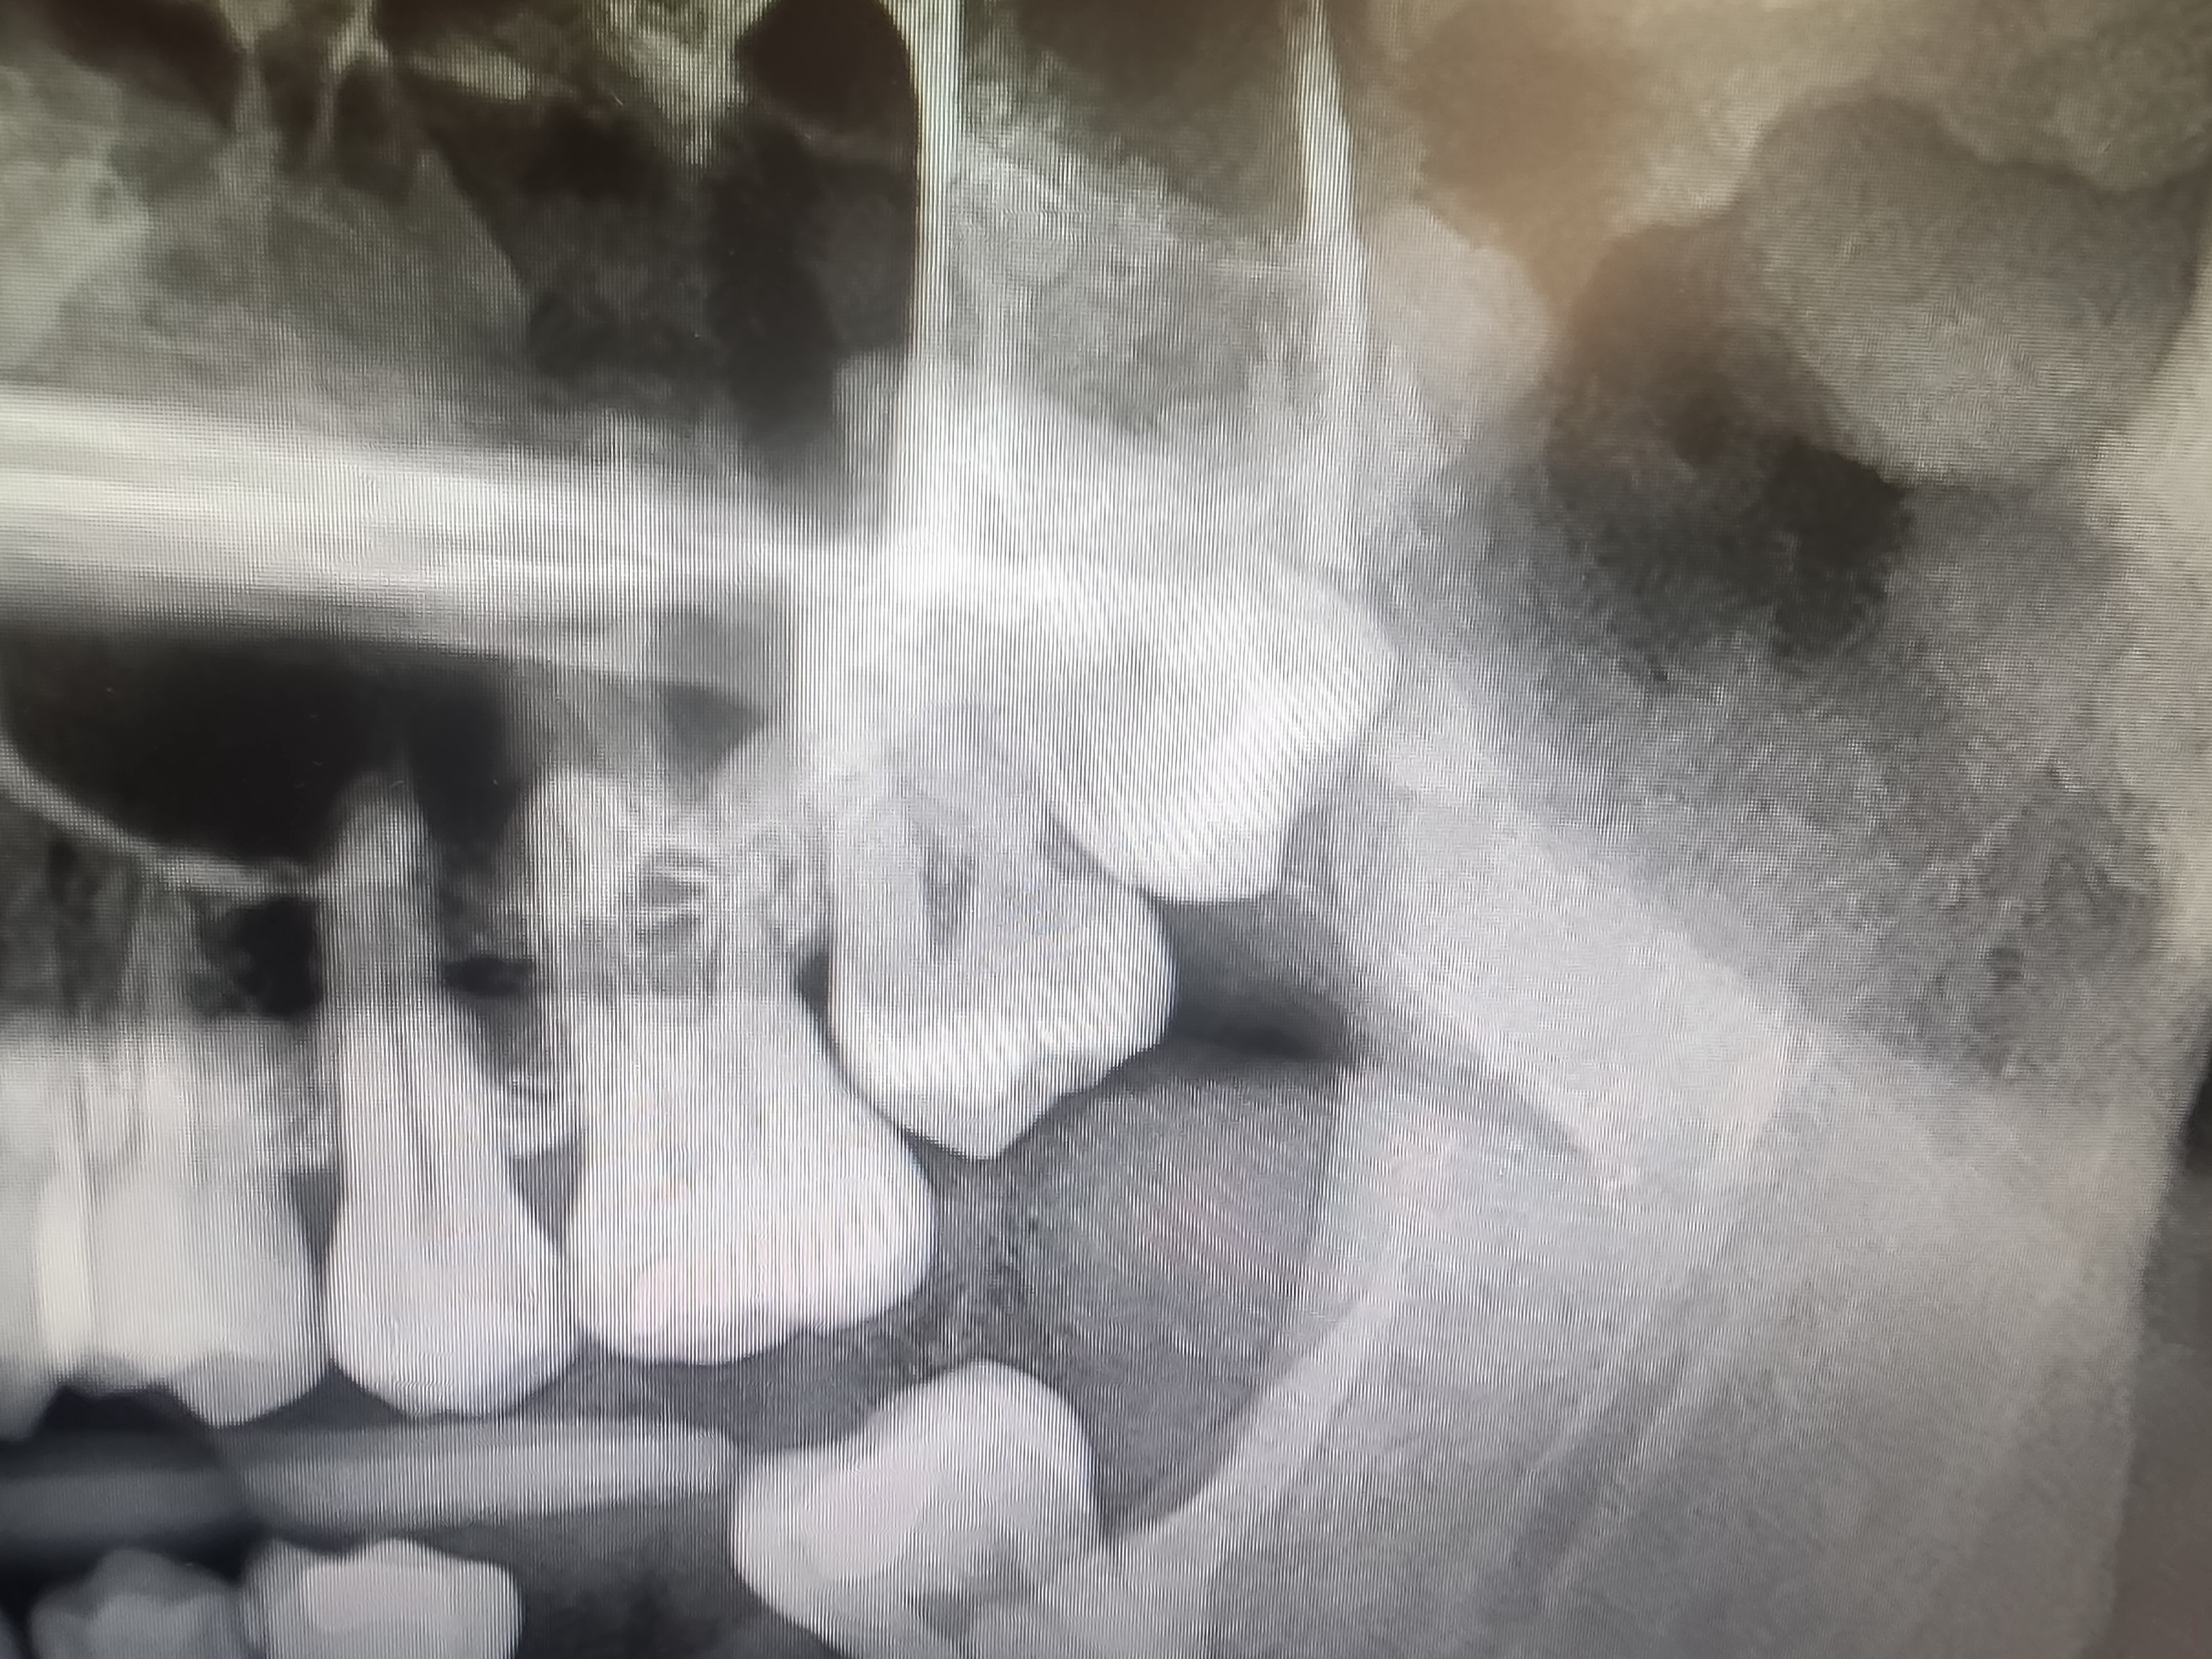

I am trying to raise money for an extremely complicated, but urgent dental surgery to remove an impacted wisdom tooth from my jaw. Unfortunately, I was not blessed with the greatest teeth.

My upper left was left untouched by previous surgeons, insisting that it wouldn't cause any issues. Here I am, 10 years later, with a hairline fracture in my jaw because there is nowhere for it to go. Sounds fun, right? The new surgeon is giving me a significant discount due to being on medicaid, but it still leaves a significant amount of nearly $3000 that I just do not have, which is a big part of why I've been putting this off. Unfortunately, it cannot be delayed any longer.